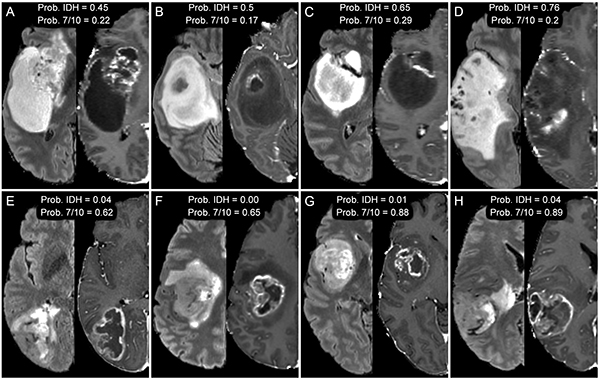

EC: My primary project is focused on predicting the presence of clinically relevant genetic biomarkers in glioblastoma using preoperative brain MRI. The idea is to use non-invasive imaging (rather than brain biopsy or resection) to determine important genetic characteristics of this aggressive form of brain cancer that can help guide treatment and inform prognosis.

EC: Glioblastoma is the most common form of brain cancer and has a very poor prognosis. My project, if successful, could allow early recognition of different molecular subtypes of glioblastoma that can benefit from specific targeted therapies without the need for invasive biopsy or resection, which is not always possible or desirable for patients. I imagine my work and other work like it allowing us to non-invasively stratify patients into different prognosis groups and direct them towards the best therapy choice at the time of tumor diagnosis rather than weeks to months later when they can get a biopsy or tumor resection.